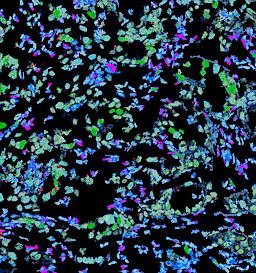

Pancreatic ductal adenocarcinoma is a lethal disease with limited treatment options and poor survival. We studied 83 spatial samples from 31 patients (11 treatment-naïve and 20 treated) using single-cell/nucleus RNA sequencing, bulk-proteogenomics, spatial transcriptomics and cellular imaging. Subpopulations of tumor cells exhibited signatures of proliferation, KRAS signaling, cell stress and epithelial-to-mesenchymal transition. Mapping mutations and copy number events distinguished tumor populations from normal and transitional cells, including acinar-to-ductal metaplasia and pancreatic intraepithelial neoplasia. Pathology-assisted deconvolution of spatial transcriptomic data identified tumor and transitional subpopulations with distinct histological features. We showed coordinated expression of TIGIT in exhausted and regulatory T cells and Nectin in tumor cells. Chemo-resistant samples contain a threefold enrichment of inflammatory cancer-associated fibroblasts that upregulate metallothioneins. Our study reveals a deeper understanding of the intricate substructure of pancreatic ductal adenocarcinoma tumors that could help improve therapy for patients with this disease.